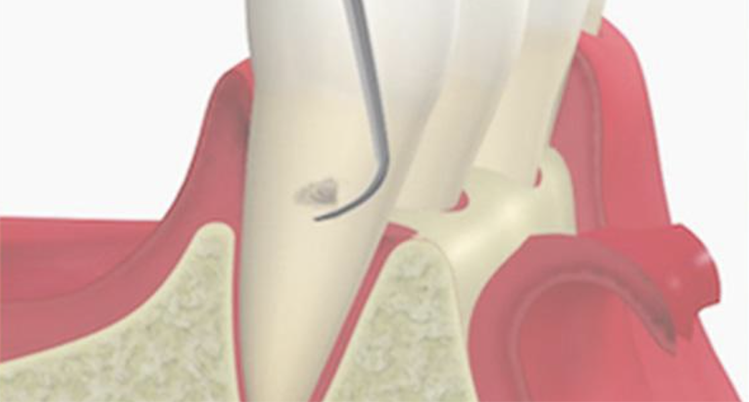

3. SRP

(スケーリング・ルートプレーニング)

専用の器具を使って、歯ぐきの中にある汚れを除去して、歯の根っこ部分の表面を汚れの付着が起こりにくい状態に仕上げる処置です。

主に、歯ぐきの中にまで歯石が入り込んでいる中等度以上の患者さまに対して行います。痛みが強い場合は、麻酔をして行うこともあります。

歯と歯茎の間の汚れをかき出すイメージイラスト